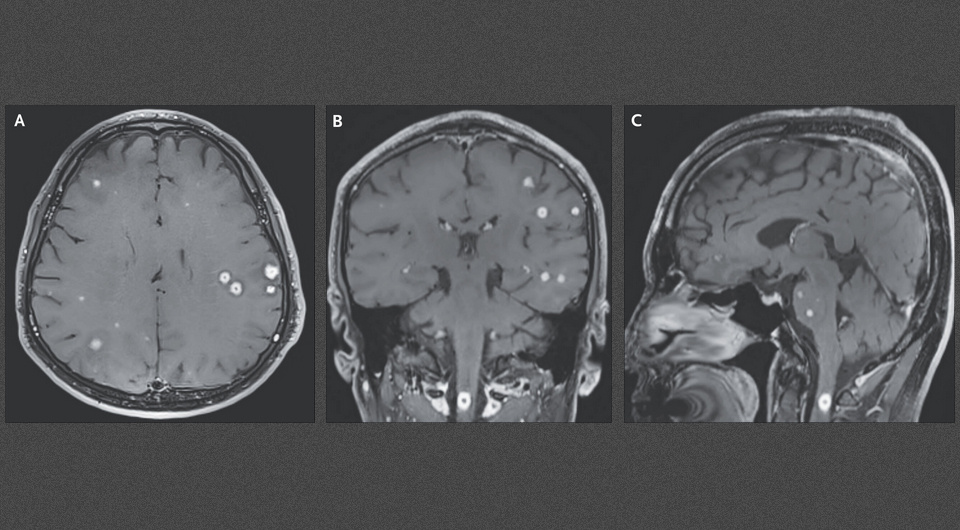

В корейскую клинику поступил 57-летний мужчина, ранее лечившийся от туберкулеза, с жалобами на головную боль, боль в шее и покалывание в кисти правой руки в течение двух недель. При осмотре определялась сниженная сила хвата правой руки. Компьютерная томография грудной клетки выявила милиарные узлы. На МРТ головы с контрастным усилением наблюдался феномен «звездного неба» — многочисленные мелкие сферические узлы с периферическим усилением сигнала в больших полушариях, базальных ганглиях, мозжечке и стволе мозга, а также в верхних отделах спинного мозга с окружающим отеком. Вовлечения мягких мозговых оболочек не наблюдалось. Анализ цереброспинальной жидкости был нормальным, бактерии из нее не высевались. Посев мокроты оказался положительным на туберкулезную микобактерию (Mycobacterium tuberculosis). Врачи Ин Сук Пэ (In-Suk Bae) и Юн Кхи Парк (Yung Ki Park) из Медцентров Ыльджи в Новонгу и Ыйджонбу описали этот случай в New England Journal of Medicine.

In-Suk Bae, Yung Ki Park / NEJM, 2025

По результатам обследования пациенту поставили диагноз туберкулем центральной нервной системы на фоне милиарного туберкулеза легких. Туберкулемы центральной нервной системы представляют собой очаги гранулематозного воспаления в местах проникновения микобактерий через кровь из первичного очага, без лечения они со временем увеличиваются в размерах и подвергаются казеозному некрозу и кальцификации. Они могут сопровождаться или (как в этом случае) не сопровождаться туберкулезным менингитом. Мужчине назначили схему антимикобактериальной терапии и дексаметазон. Примерно через месяц симптомы заболевания начали уменьшаться, при контрольном обследовании через 18 месяцев они полностью отсутствовали, и МРТ головы была нормальной. Феномен «звездного неба» на МРТ чаще всего наблюдается при цистицеркозе — инвазии мозга личинками обитающего в кишечнике свиного цепня, но может возникать и при туберкулемах, шистосомозе, лихорадке Скалистых гор, японском энцефалите и некоторых других поражениях центральной нервной системы. В свою очередь, воспаление твердых мозговых оболочек может проявляться на МРТ признаком ночной Эйфелевой башни.